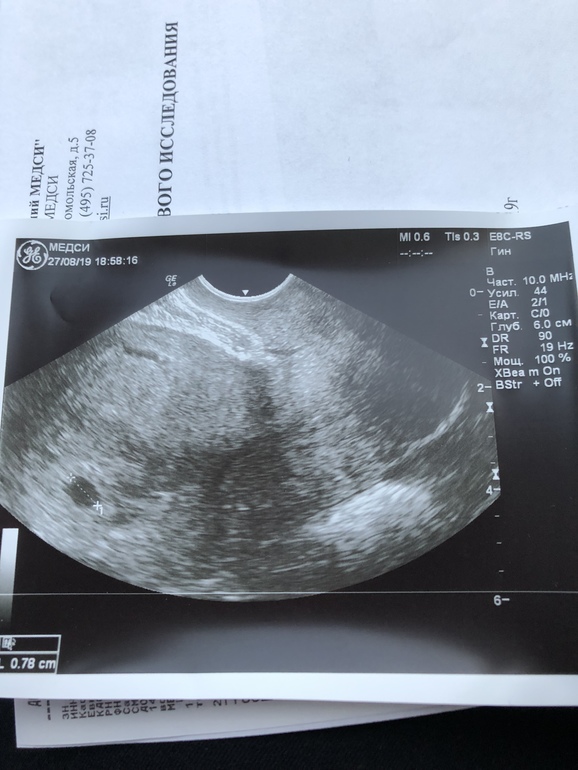

И вот, сегодня сходила на узи. Срок 5 недель и 4 дня. Попросили придти повторно через 2 недели слушать сердцебиение.